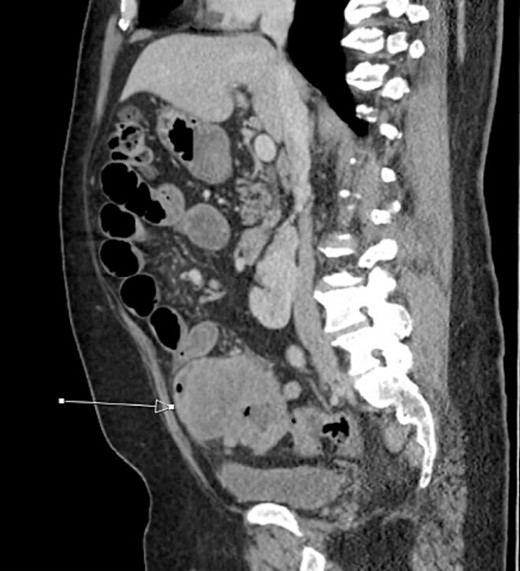

The patient was initially managed nonoperatively with conservative measures including nasogastric (NG) tube decompression, pain control, and serial abdominal exams. Surgery was consulted once CT imaging was obtained (Figs 1–3) and recommended that the patient undergo surgery to resect the identified mass and relieve the obstruction. During the surgical exploration, a mass originating from the terminal ilium was identified that was densely adhered to the peritoneum, bladder, and sigmoid colon, requiring careful dissection. The mass, three lymph nodes, and 29 cm of associated small bowel segment was resected with grossly negative margins, with the mass measuring 7 cm × 8 cm × 9.5 cm. A side-to-side anastomosis was created and the specimens were sent to pathology for further investigation. Postoperatively the patient was hospitalized for 7 days for pain control and monitoring. On postoperative day eight he was discharged with follow up appointments with oncology, general surgery, and a referral to an academic cancer center.

Initial CT imaging, sagittal cut, showing necrotic mass causing small bowel obstruction.